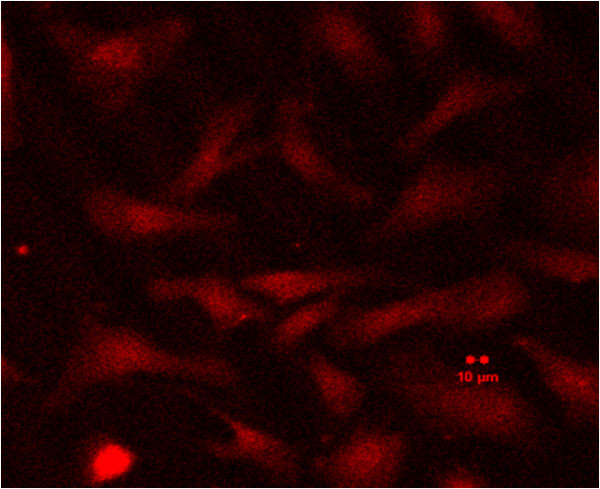

免疫熒光+細胞轉染

免疫熒光

細胞轉染

2h

12h

48h